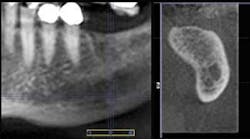

The small detail that “isn't so” can deter the successful outcome of an implant procedure. General practitioners must be armed with the most detailed information possible that can increase their comfort level in placing implants. Sometimes, a 2-D pan cannot provide insight into the 3-dimensional shape of the bone, which is imperative when placing implants. Some anomalies just can't be discerned in two dimensions, and 3-D technology adds depth to our diagnosis, planning, and success. My GXCB-500, which scans just the areas I need as a general dentist, delivers this information. A colleague and fellow “500” owner, Dr. Gary Henkel of Horsham, Pa., shared some images of a patient where 3-D saved the day.